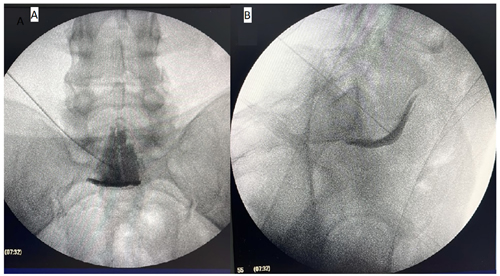

Este estudio tiene como objetivo mostrar los resultados del bloqueo del plexo hipogástrico superior (Figura 2) para el manejo del dolor pélvico crónico. Se reporta la reducción significativa del dolor (menos del 50 % de EVA inicial) solo en el 45 % de los pacientes al primer mes, y en el 36 % y 23 % a los meses 3 y 6, respectivamente. A su vez, el porcentaje de mejoría promedio de EVA al primer mes fue de 37,3 %, de 30 % al tercer mes y del 20 % al sexto mes. Nuestro estudio difiere de los resultados encontrados por otros autores (9,10,11), quienes han reportado mayor efectividad del bloqueo para dolor pélvico crónico, pero dichas diferencias pueden deberse a la población intervenida, con diferentes características, como por ejemplo la etiología oncológica, técnicas diferentes (uso de guía tomográfica) y finalmente a diferentes operadores.

Fig. 2. Imagen fluoroscópica del bloqueo hipogástrico superior. A: vista anteroposterior, medio de contraste en línea media. B: vista lateral, medio de contraste anterior a espacio L5S1 y al promontorio sacro.